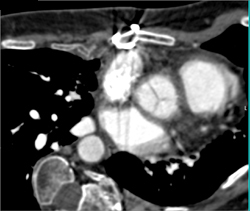

Bladder Perforation